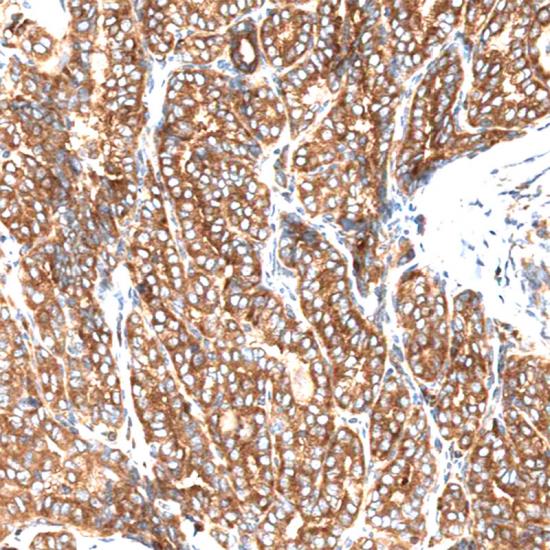

BRAF(V600E)

甲狀腺癌

BRAF是人類最重要的原癌基因之一,大約8%的人類腫瘤發(fā)生BRAF突變。BRAF絕大部分突變形式為BRAF(V600E)突變,主要發(fā)生于黑色素瘤、結(jié)腸癌和甲狀腺癌中。該突變導(dǎo)致下游MEK-ERK 信號(hào)通路持續(xù)激活,對(duì)腫瘤的生長(zhǎng)增殖和侵襲轉(zhuǎn)移至關(guān)重要,是抗黑色素瘤等BRAF(V600E)突變腫瘤特效新藥Vemurafenib和Dabrafenib的有效作用靶標(biāo)之一。